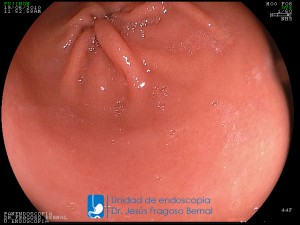

La Unidad de Endoscopía fue creada en 2002 por el Dr. Jesús Fragoso Bernal, es pionera en el estado por la utilización de la tecnología más avanzada, que nos permite ofrecer servicios integrales de diagnóstico y tratamiento para las enfermedades del aparato digestivo.

El profesionalismo de nuestro personal, altamente especializado, se distingue por la calidad y calidez de nuestros servicios con el objetivo de brindar una atención de excelencia en el ambiente más confortable para comodidad y seguridad de nuestros pacientes.

"La Unidad de Endoscopía se ha caracterizado por un progreso continuo desde su inicio marcando la pauta en los procedimientos endoscópicos en el estado de Tlaxcala y estando siempre a la vanguardia tecnológica."

Dr. Jesús Fragoso Bernal